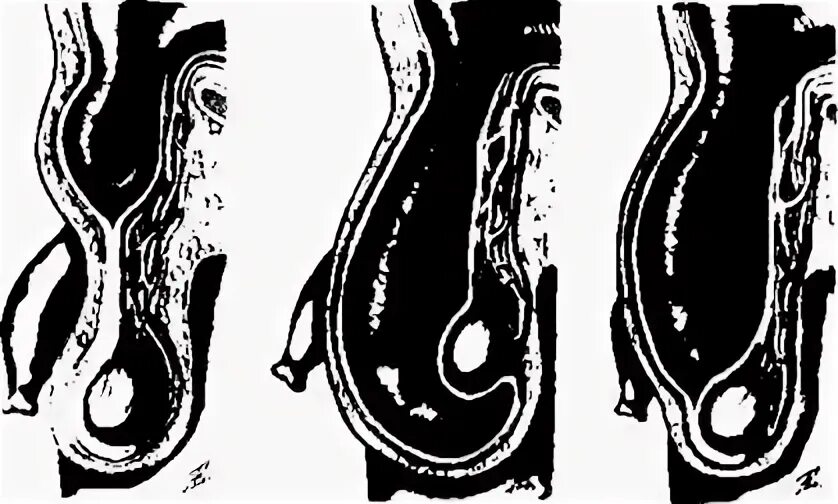

Симптомы мошоночной грыжи